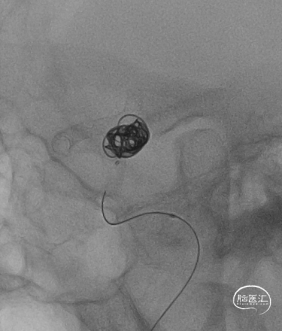

8F导引导管、6F颅内支撑导管同轴建立稳定通路,在导丝引导下,将6F颅内支撑导管送至右侧颈内动脉C4海绵窦段,以便提供颅内稳定的支持。选择合适工作角度,在Synchro-14微导丝的指引下,将XT-27支架微导管送至右侧大脑中动脉M2段,并预埋栓塞微导管在动脉瘤腔内,计划在密网支架释放后对动脉瘤进行弹簧圈疏松填塞。将预期血管内直径/长度为3.5mm*20mm的Nuva®密网支架沿着XT-27支架微导管输送,支架顺利打开。支架完全释放后造影显示支架显影清晰,形态良好,无贴壁不良。随后经栓塞微导管填入2枚弹簧圈对动脉瘤进行疏松填塞,撤出微导丝,手术结束。

【Nuva支架完全打开】